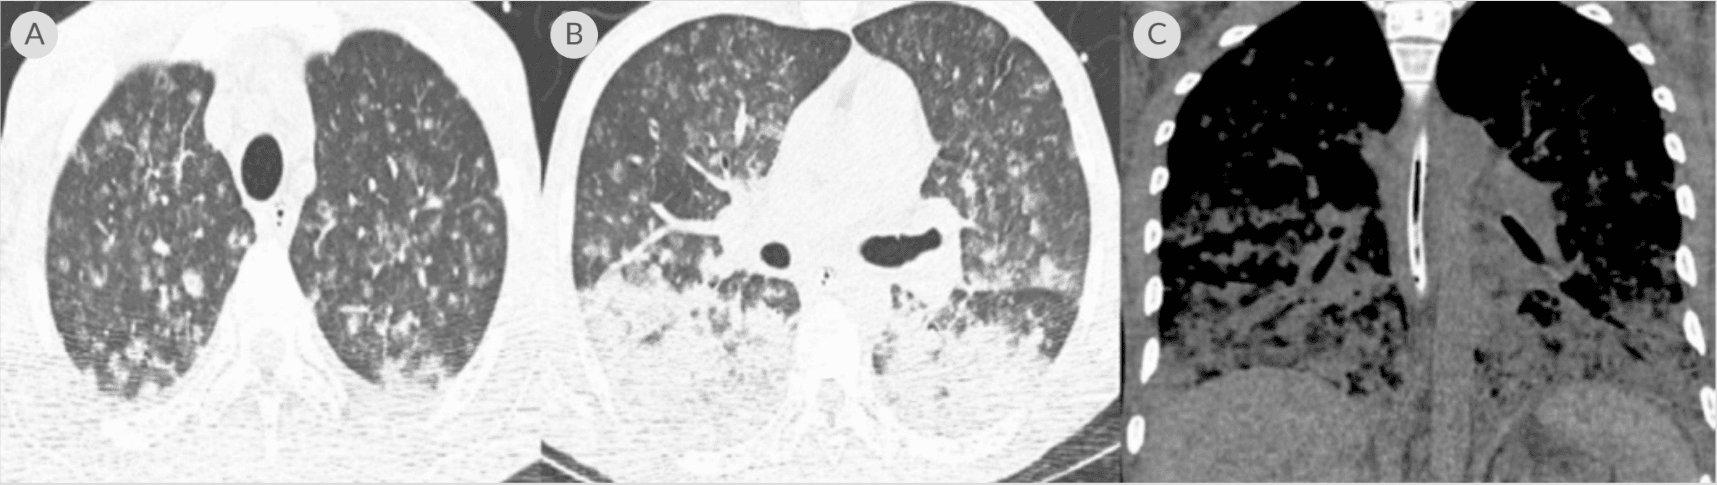

39 years old with untreated HIV infection and respiratory failure requiring mechanical ventilation with an unclear etiology.

Tests Performed: Diagnostic tests performed for evaluation of pneumonia and other etiologies included absolute CD4 count of 6, HIV viral load of 332,909 copies/ml, CMV IgG positive; CXR with bilateral multinodular changes, chest CT with miliary lesions, brain MRI with multiple ring enhancing lesions; negative testing included: blood and BAL cultures; VZV, syphilis, and tuberculosis studies; Histoplasma/ Aspergillus/ Legionella/ Cryptococcus/ Influenza antigens.

(A) CT chest axial lung window showing miliary changes in both lungs; (B) CT chest axial lung window showing several nodules with developing central cavitation and bilateral consolidation; (C) coronal window showing bibasilar airspace disease with confluent consolidation throughout the lung bases5

Karius Spectrum Test Result: Toxoplasma gondii

Outcome: Started 6-week course of pyrimethamine/sulfadiazine, discontinued piperacillin/tazobactam; resulting in significant clinical improvement allowing the patient to be started on antiretroviral therapy.